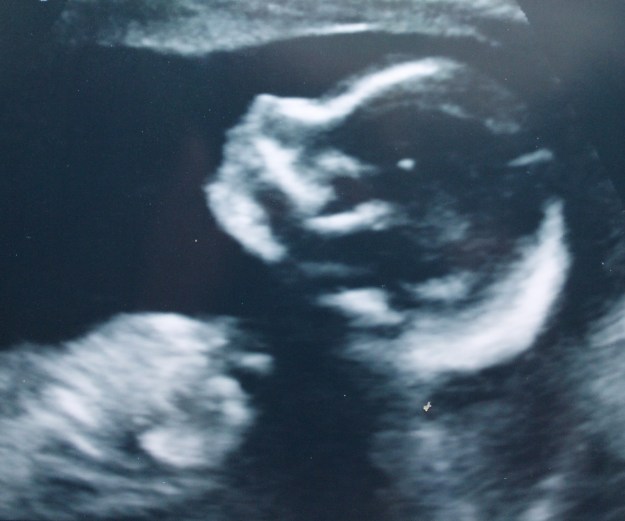

In short, the project I’m working on is… a baby!

There he is!  He doesn’t have a name yet, and isn’t due to be born until the beginning of April, but he’s very much making his presence known (I’m afraid of stretching out all my sweaters, so I’m down to cardigans only), and has currently wedged himself uncomfortably up in my rib cage.

(I wonder how many of you guessed something was up with all the baby sweater talk.)